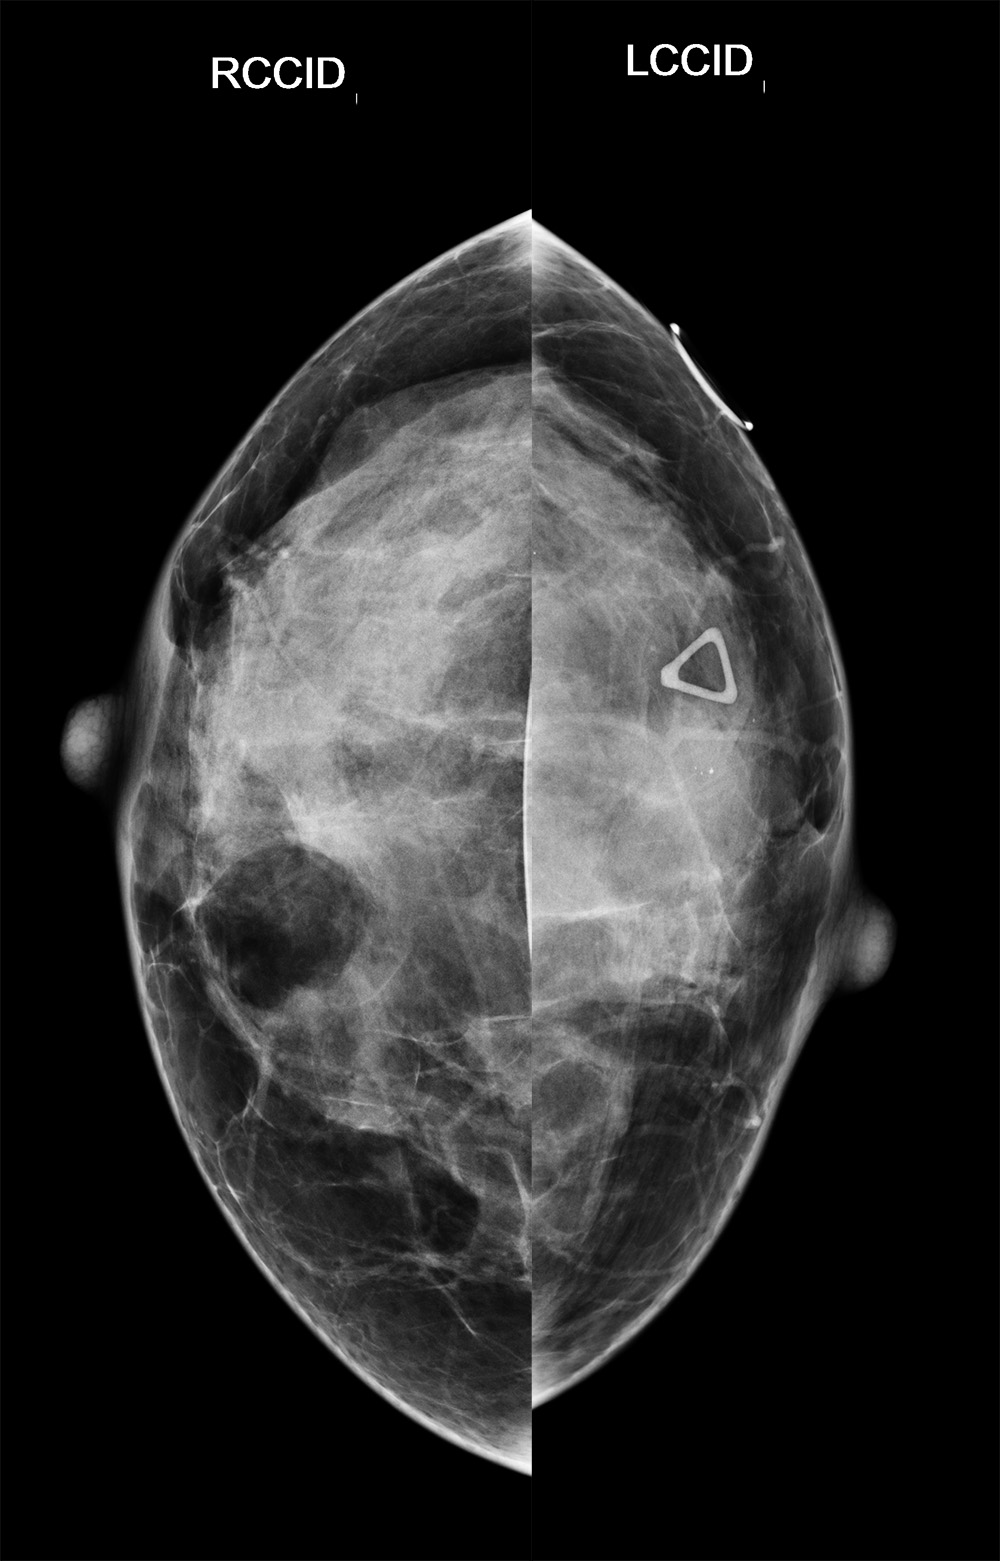

◂Breast Anatomy